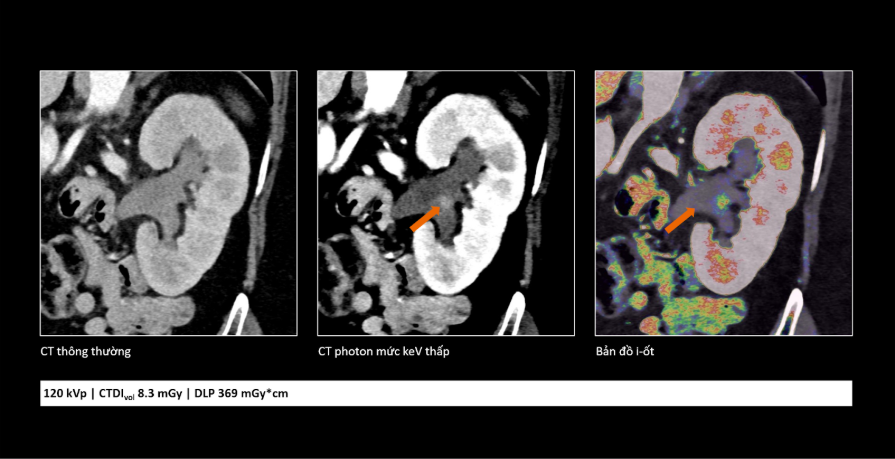

Công nghệ cắt lớp vi tính lượng tử: Mở ra cơ hội phát hiện sớm và điều trị chính xác hơn cho người bệnh- Ảnh 3.

So sánh cho thấy công nghệ cắt lớp vi tính lượng tử không chỉ giúp hình ảnh rõ hơn mà còn cung cấp thêm thông tin, hỗ trợ bác sĩ đánh giá tổn thương chính xác hơn.